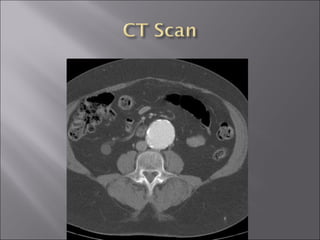

Pain: most common, at hypogastrium or back, not affected by movement 75 % asymptomatic Rupture triad : abdominal or back pain; palpable/ pulsatile abdominal mass; hypotension (<1/3 cases) Bruit (+/-) Abdomianl echo, CT, MRA, aortography

Pain: most common,at hypogastrium or back, not affected by movement 75 % asymptomatic Rupture triad : abdominal or back pain; palpable/ pulsatile abdominal mass; hypotension (<1/3 cases) Bruit (+/-) Abdomianl echo, CT, MRA, aortography